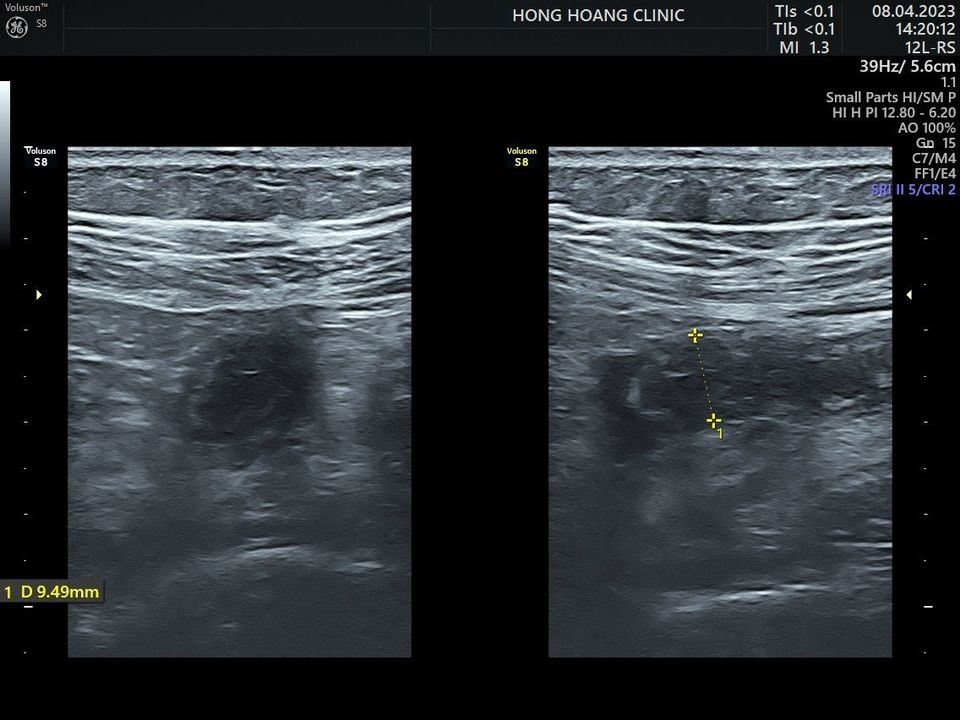

Vừa rồi, tại Phòng khám đa khoa Hồng Hoàng có trường hợp thai phụ 28 tuần đến khám với triệu chứng bị đau bụng. Sau khi thăm khám, làm xét nghiệm máu, siêu âm kiểm tra thì phát hiện thai phụ bị đau ruột thừa. Phòng khám đã tư vấn thai phụ đến bệnh viện để có phương pháp điều trị phù hợp.